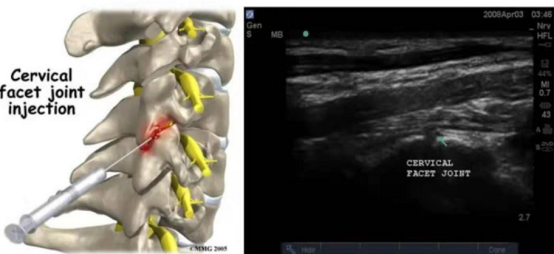

肌骨超声不仅应用于肌骨系统疾病的诊断,而且与多学科合作开展超声引导下的微创“可视化”介入治疗,显著减少并发症、提高治疗效果。目前功能科开展的超声引导下治疗冻结肩、足底筋膜炎、腱鞘炎、滑囊炎、棘上韧带炎、筋膜炎、梨状肌综合征、腰椎小关节紊乱导致的下腰痛等微创治疗效果显著。在超声引导下的穿刺可以实时显示微创介入操作的全过程,从进针路径、靶器官治疗位置、周围软组织关系显示都非常直接,有效避免并减少相邻重要结构的损伤。超声引导下的介入治疗比盲穿更具安全性和精确性,在实际工作中,超声引导的介入治疗可明显减轻穿刺引起的疼痛。

图5 冻结肩治疗前 治疗中 治疗后

图6 脊神经后支阻滞 针尖至横突根部

图7 颈椎小关节源性疼痛 关节突关节注射